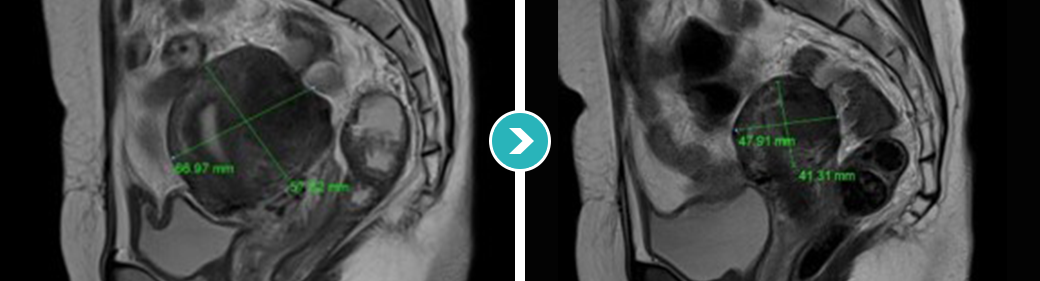

심한 생리통과 항문통증으로 자궁선근증이 진단되어 자궁선근증 하이푸 치료를 위해 입원하셨습니다.

하이푸 시술전 MRI사진상 자궁은 6.5크기로 커져서 자궁후벽을 중심으로 자궁선근증성 변화가 관찰됩니다.

아래의 MRI 사진은 자궁선근증 하이푸 시술 전후의 사진을 비교한 사진입니다. 자궁선근증 하이푸 치료후 90%이상 치료되어 치료부위가 회색과 검은색으로

나타나며, 차후에 좋은 경과를 기대하며 가장자리의 잔여병변은 호르몬 치료하면서 경과관찰 하시도록 하였습니다.